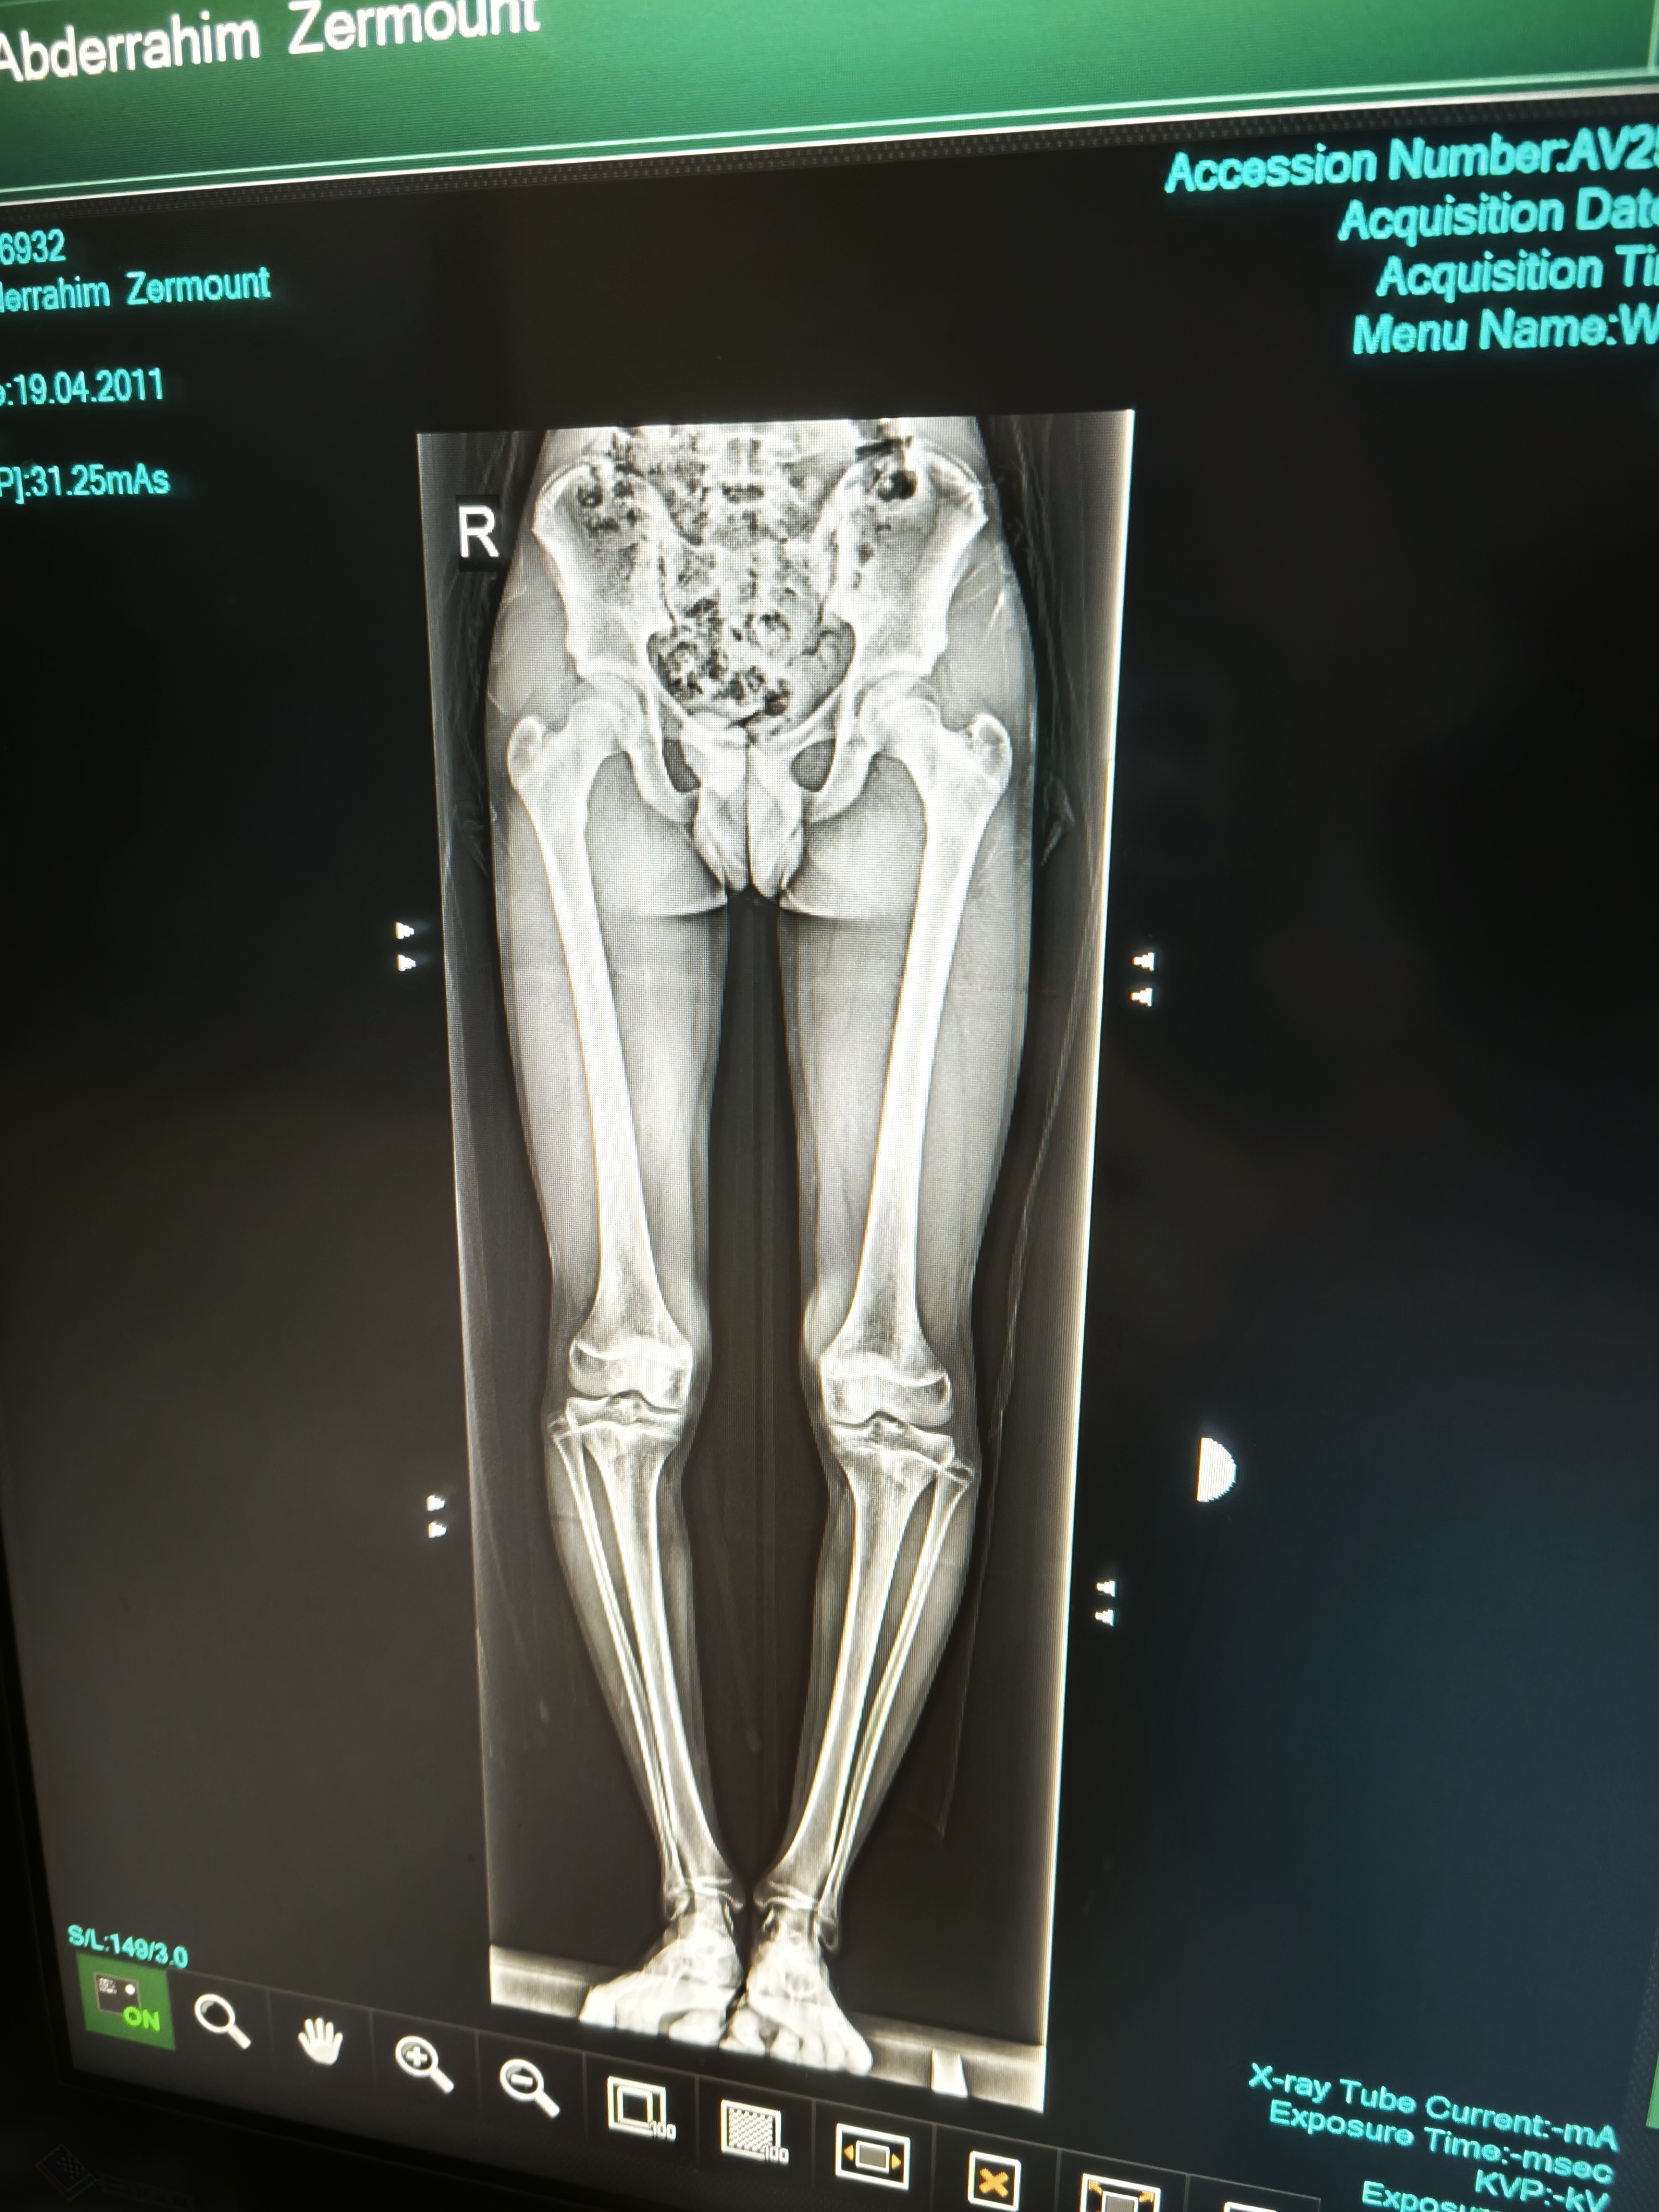

My growth plates are gonna end in like 6 months how much of HGH should I inject I'm just blasting everything I can to grow as tall as possible

10000 IU’s twice a dayMy growth plates are gonna end in like 6 months how much of HGH should I inject I'm just blasting everything I can to grow as tall as possible View attachment 4382158